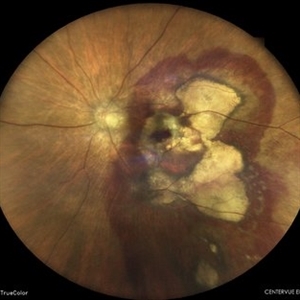

Subretinal Hemorrhage

Subretinal Hemorrhage

Feb 28 2023 by Akansha Sharma

Color fundus photograph of an 84-year old male with subretinal hemorrhage associated with areas of scarring.

Photographer: Dr. Urmil Shah, Dr. Denish Patel, Dr. Akansha Sharma, Bharati Eye Hospital, Ahmedabad, Gujarat

Condition/keywords: choroidal neovascularization (CNV), subretinal hemorrhage